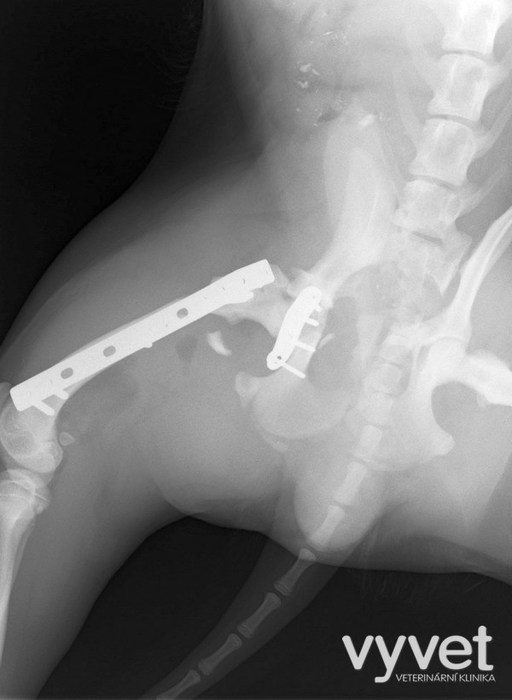

Nejčastějším problémem dlouhých kostí jsou zlomeniny (fraktury)

Rozdělujeme je do několika skupin podle charakteru, množství fragmentů, průběhu linie lomu, dislokace, stability atd.

Je mnoho popsaných metod fixací fraktur. Neinvazivní metodou je přikládání fixačních obvazů a kastů. Tento typ fixace však není ideální, protože nejsme schopni u zvířat zabezpečit dostatečně dlouhou dobu klidu pro srůst kosti. Ideální metodou je invazivnější přístup a to chirurgická repozice s následnou fixací osteosyntetickým materiálem.

Na našem pracovišti používáme zejména ploténky a hřeby.